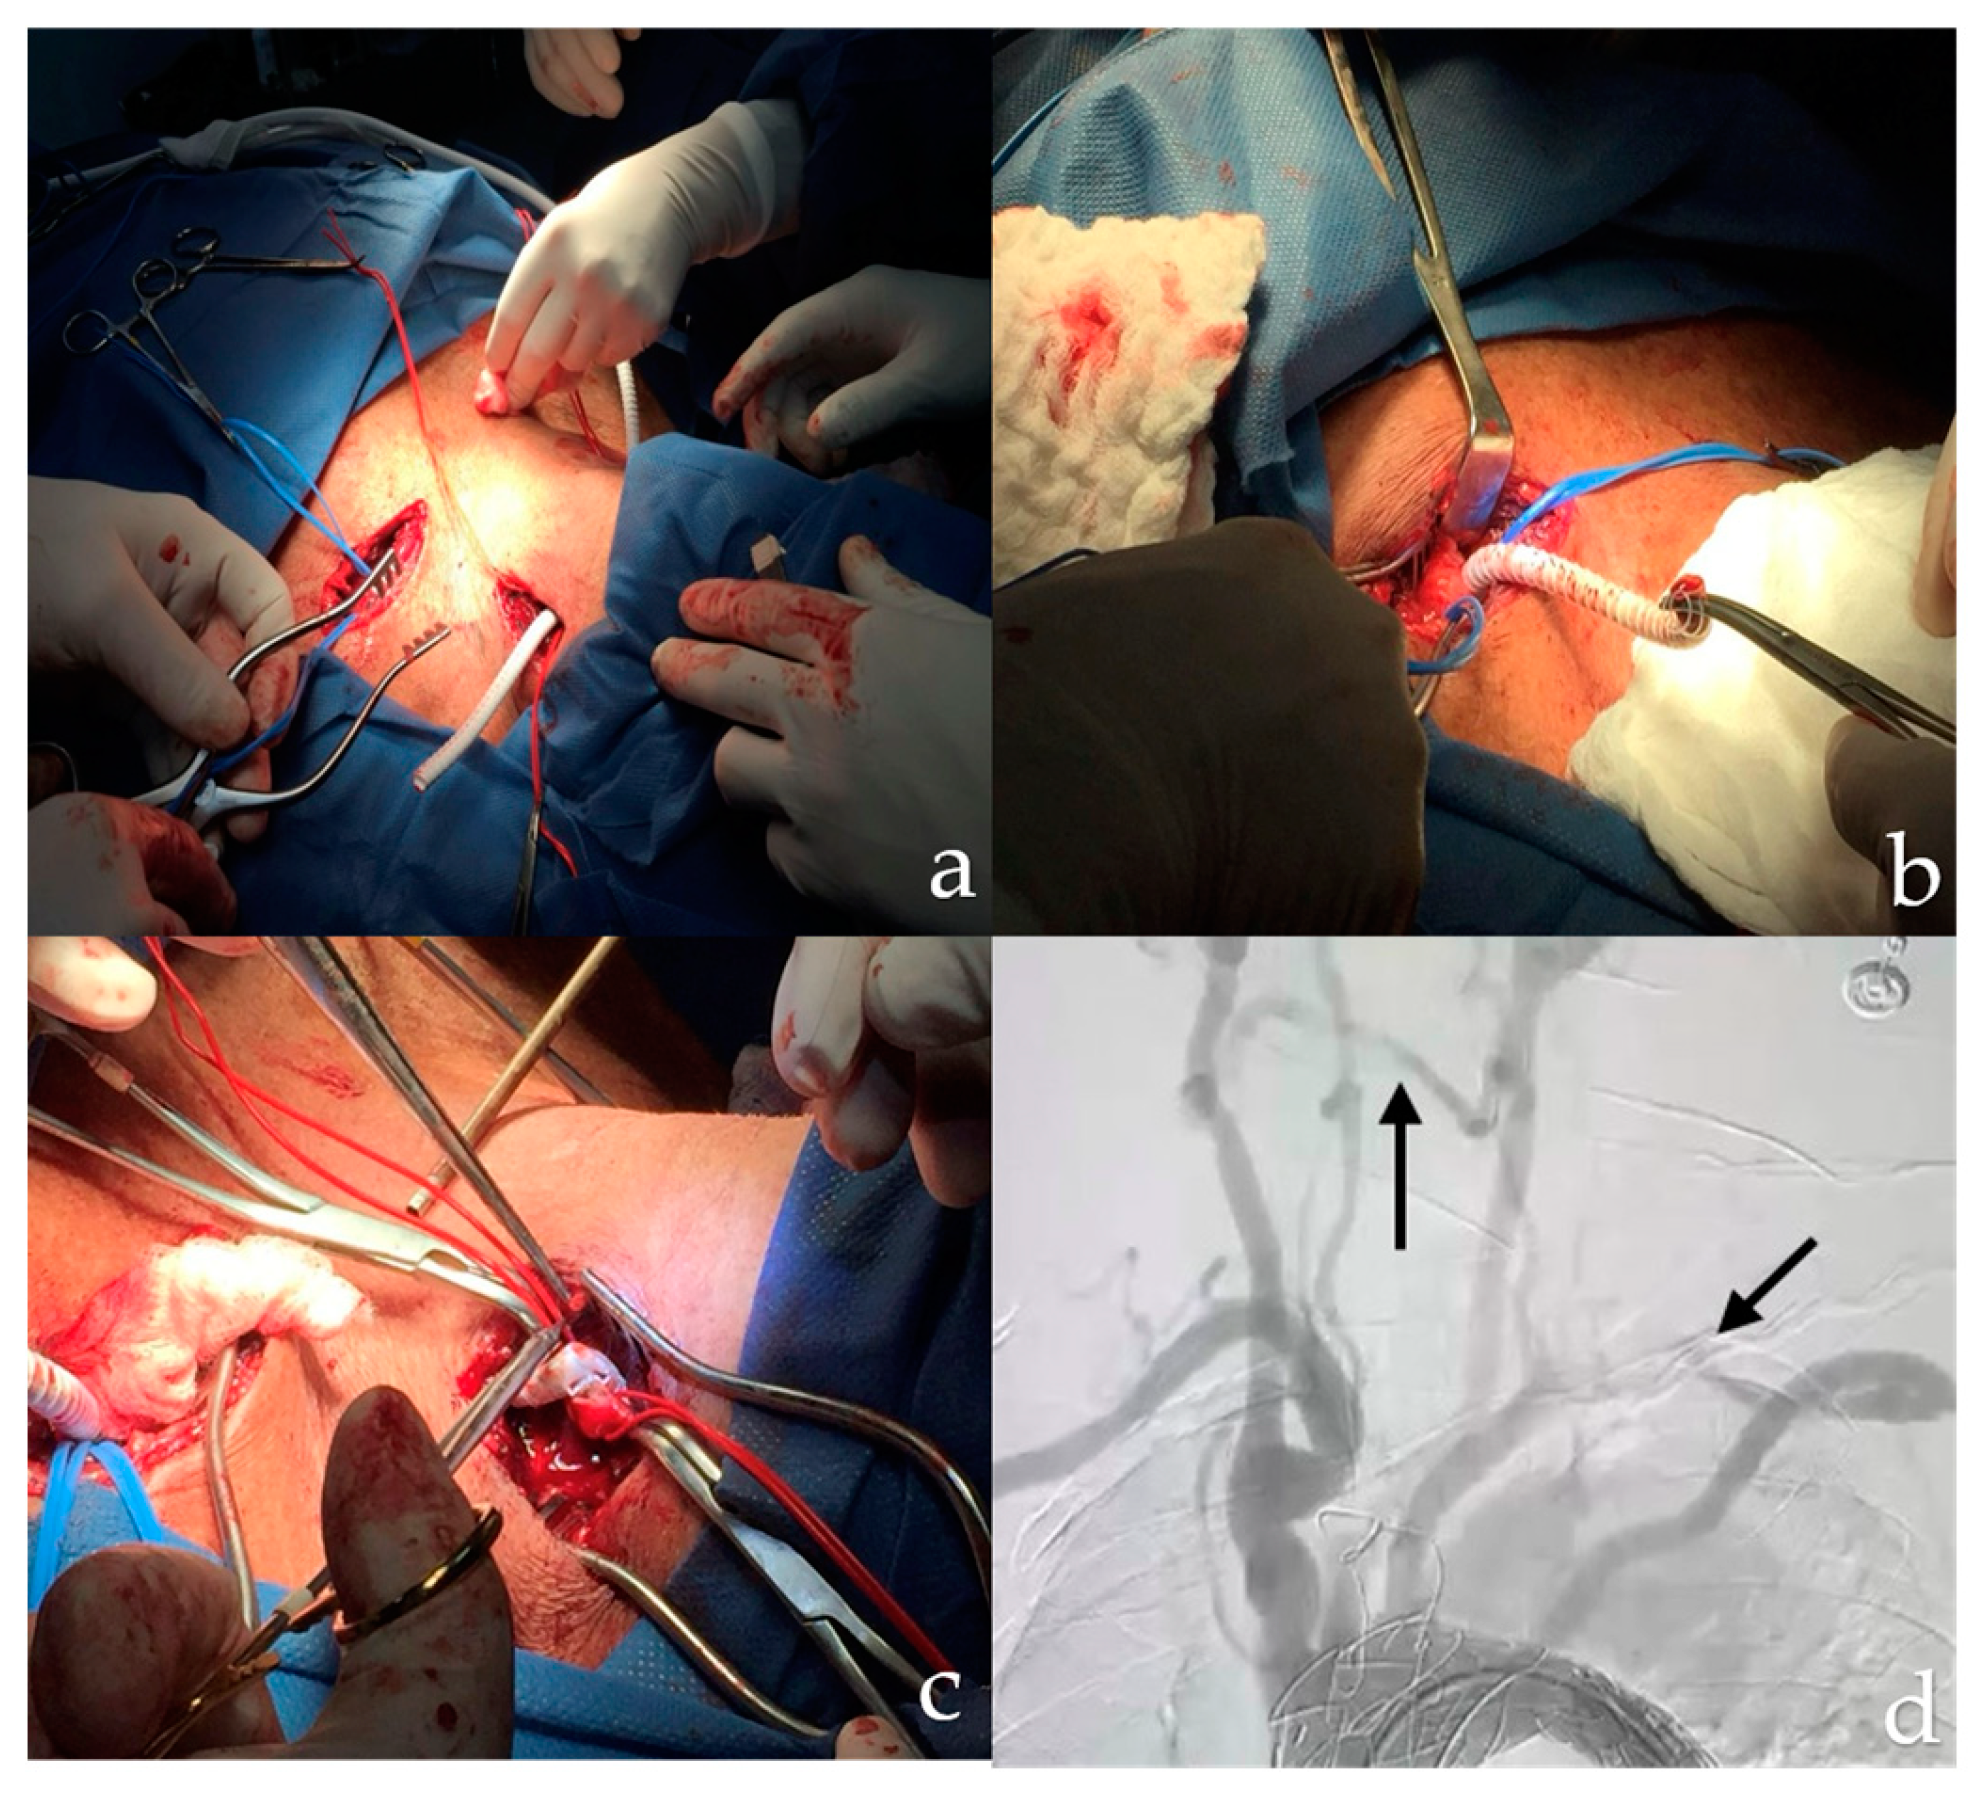

On postoperative day 8, the patient reported pain in the right lower extremity, prompting computed tomography angiography (CTA). This revealed a Stanford B-type aortic dissection extending into the abdominal aorta and right external iliac artery (Figure 2).

Figure 2. Stanford B aortic dissection (a) Thoracic aortic dissection (b, c, d) Abdominal aortic dissection.